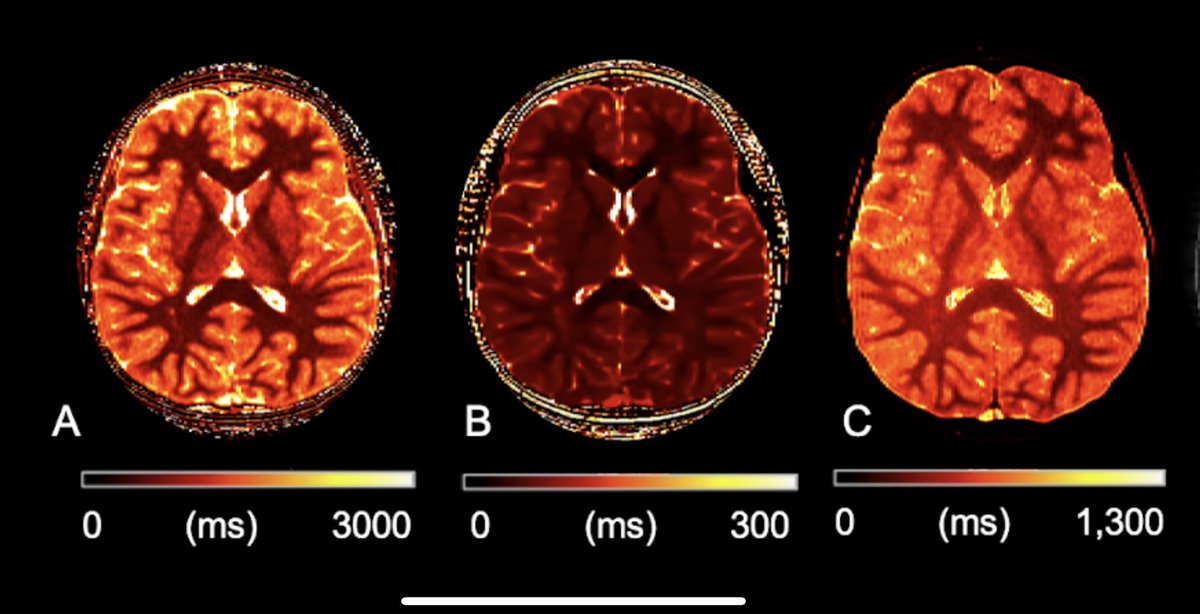

Congratulations to Camilo Calixto and collaborators María Camila Cortés Albornoz , Fedel Machado Rivas , Onur Afacan on such interesting work--- and beautiful illustrations! -- Joint work from Pediatric Imaging Research Center Boston Children's Radiology - pubmed.ncbi.nlm.nih.gov/37842932/

New work by BCH (Boston Children's Radiology) / MGH Pediatric Imaging Research Center is on 🔥 Using DTI to analyze microstructure of the fetal brain 🧠. Congrats Camilo Calixto María Camila Cortés Albornoz Fedel Machado Rivas Onur Afacan .

The amazing María Camila Cortés Albornoz explores brain development before the 20th week of gestation. The team looked into how the brain grows in the early 2nd trimester, even before most clinical MRIs occur. Pediatric Imaging Research Center Boston Children's Radiology Onur Afacan AJNR